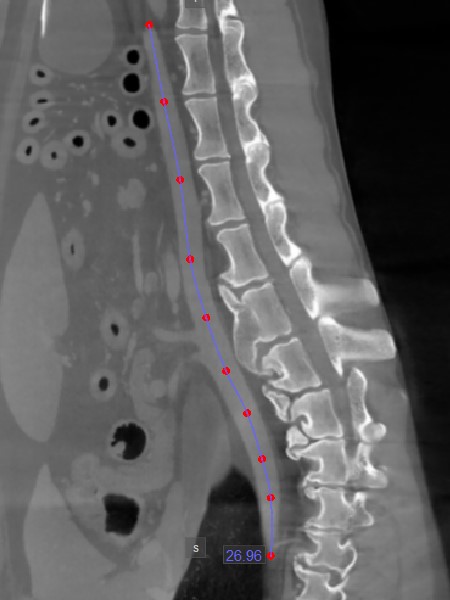

Path Length¶

The Path Length tool offers users the ability to measure the length of irregular lines or the outline of intricate shapes along a non-linear path.

Select the Path Length and assign it to one of the available mouse buttons. Start the measurement by placing points along a non-linear path on the active image slice. As the user places the points, the software

automatically connects and creates the path.

Complete the measurement by double-clicking when placing the last point of the path, or use the right mouse button to immediately calculate the path. The length of the path is displayed alongside the measurement.

Modify the path by moving one of the points describing it using the Default tool.